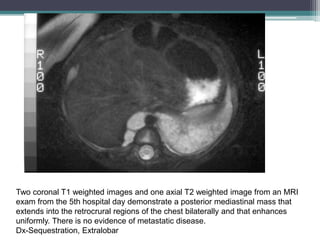

PA and lateral chest films from the day

of admission demonstrate a large

round opacity in the left lower lobe that

abuts the diaphragm

Two coronal T1 weighted images and one axial T2 weighted image from an MRI

exam from the 5th hospital day demonstrate a posterior mediastinal mass that

extends into the retrocrural regions of the chest bilaterally and that enhances

uniformly. There is no evidence of metastatic disease.

Dx-Sequestration, Extralobar